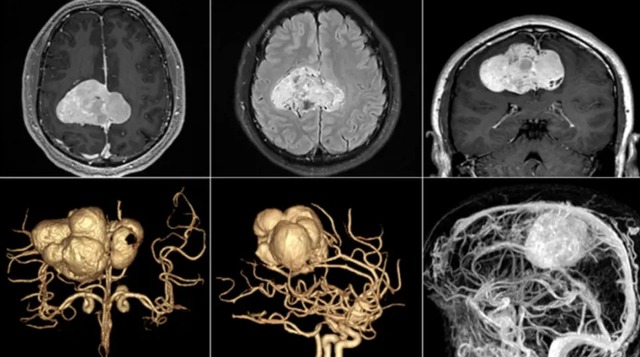

Thật không ngờ, bác sĩ xương khớp không tìm ra bệnh mà khuyên anh nên tới khoa thần kinh hoặc ung bướu. Cuối cùng, anh được phát hiện có khối u kích thước rất lớn, nằm sát vùng vận động, chèn ép dây thần kinh và mạch máu quan trọng. Tính mạng anh Vương gặp nguy hiểm, cần phải chuyển lên tuyến trên để phẫu thuật ngay lập tức.

Ca mổ của anh kéo dài tới 17 tiếng liên tục, với sự tham gia của hơn 10 y bác sĩ tại Khoa Phẫu thuật Thần kinh của Bệnh viện Liên minh trực thuộc Đại học Y Phúc Kiến (Trung Quốc). May mắn là khối u được loại bỏ thành công, sau 2 tuần hồi phục thì anh Vương đang tiếp tục vật lý trị liệu.

Tiến sĩ Lương Nhật Sinh là người chỉ đạo chính và trực tiếp phẫu thuật cho anh Vương. Ông cho biết khối u của anh là u sợi đơn độc, một dạng hiếm gặp của khối u hệ thần kinh trung ương. Khối u có đường kính 7cm, chèn ép lên vùng vận động nên gây ra cảm giác tê bì, run và yếu ở tay trái, thậm chí nửa người bên trái. Loại u, vị trí và kích thước, thời điểm phát hiện của khối u khiến ca bệnh trở thành ca cực khó, nguy hiểm và dễ để lại biến chứng.